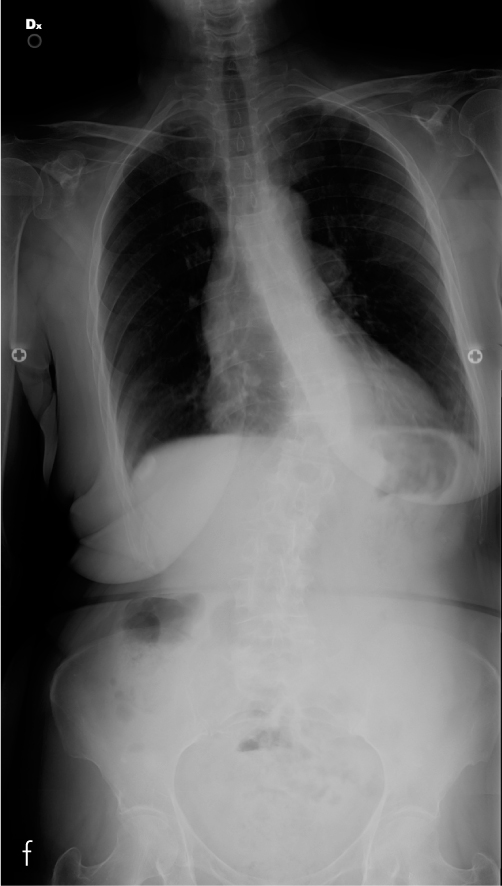

In questi casi, un attento studio pre operatorio ha permesso di distinguere i quadri di compressione radicolare da stenosi dei soli forami di coniungazione, dalle più complesse compressioni centrali. È stata valutata inoltre la presenza di scoliosi degenerativa (f) (con crollo asimmetrico del disco intervertebrale e chiusura del forame di coniugazione corrispondente) e l’eventuale presenza di disallineamento sul piano sagittale con la comparsa di spondilolistesi degenerativa.

L’estensione della laminectomia, il numero di vertebre stabilizzate e l’eventuale artrodesi anteriore (g,h) sono stati decisi in base alla sintomatologia del paziente attentamente correlata con gli esami di imaging (radiografie sotto carico, RMN e TAC), considerando anche fattori accessori quali l’età, le capacità di sopportare un intervento in ipotensione controllata e le possibilità di recupero post operatorio.